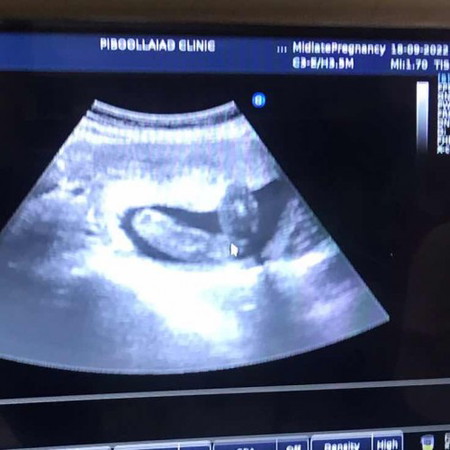

ช่วยดูหน่อยค่ะ ในรูปน้องเป็นเพศอะไรคะแม่ๆ

อยากได้ความมั่นใจในการเตรียมเสื้อผ้าค่ะ

ตอนนี้กี่วีคแล้วคะ หมอบอกเพศจะชัดตั้งแต่20วีคขึ้นไป แต่ก็อยู่ที่ท่านอนของเด็กด้วย บ้านนี้โชว์เห็นตอน16วีค ตอนนี้32วีคแล้ว ผช.100%

คุณหมอบอกเพศไหมคะ แล้วตอนนี้กี่วีคแล้วคะ

22 w ค่ะ

ไม่ชัดเลยแม่ แต่ไม่เห็นจู๋ น่าจะหญิงค่ะ

น่าจะลูกสาวค่ะแม่

น่าจะผู้หญิงนะคะ